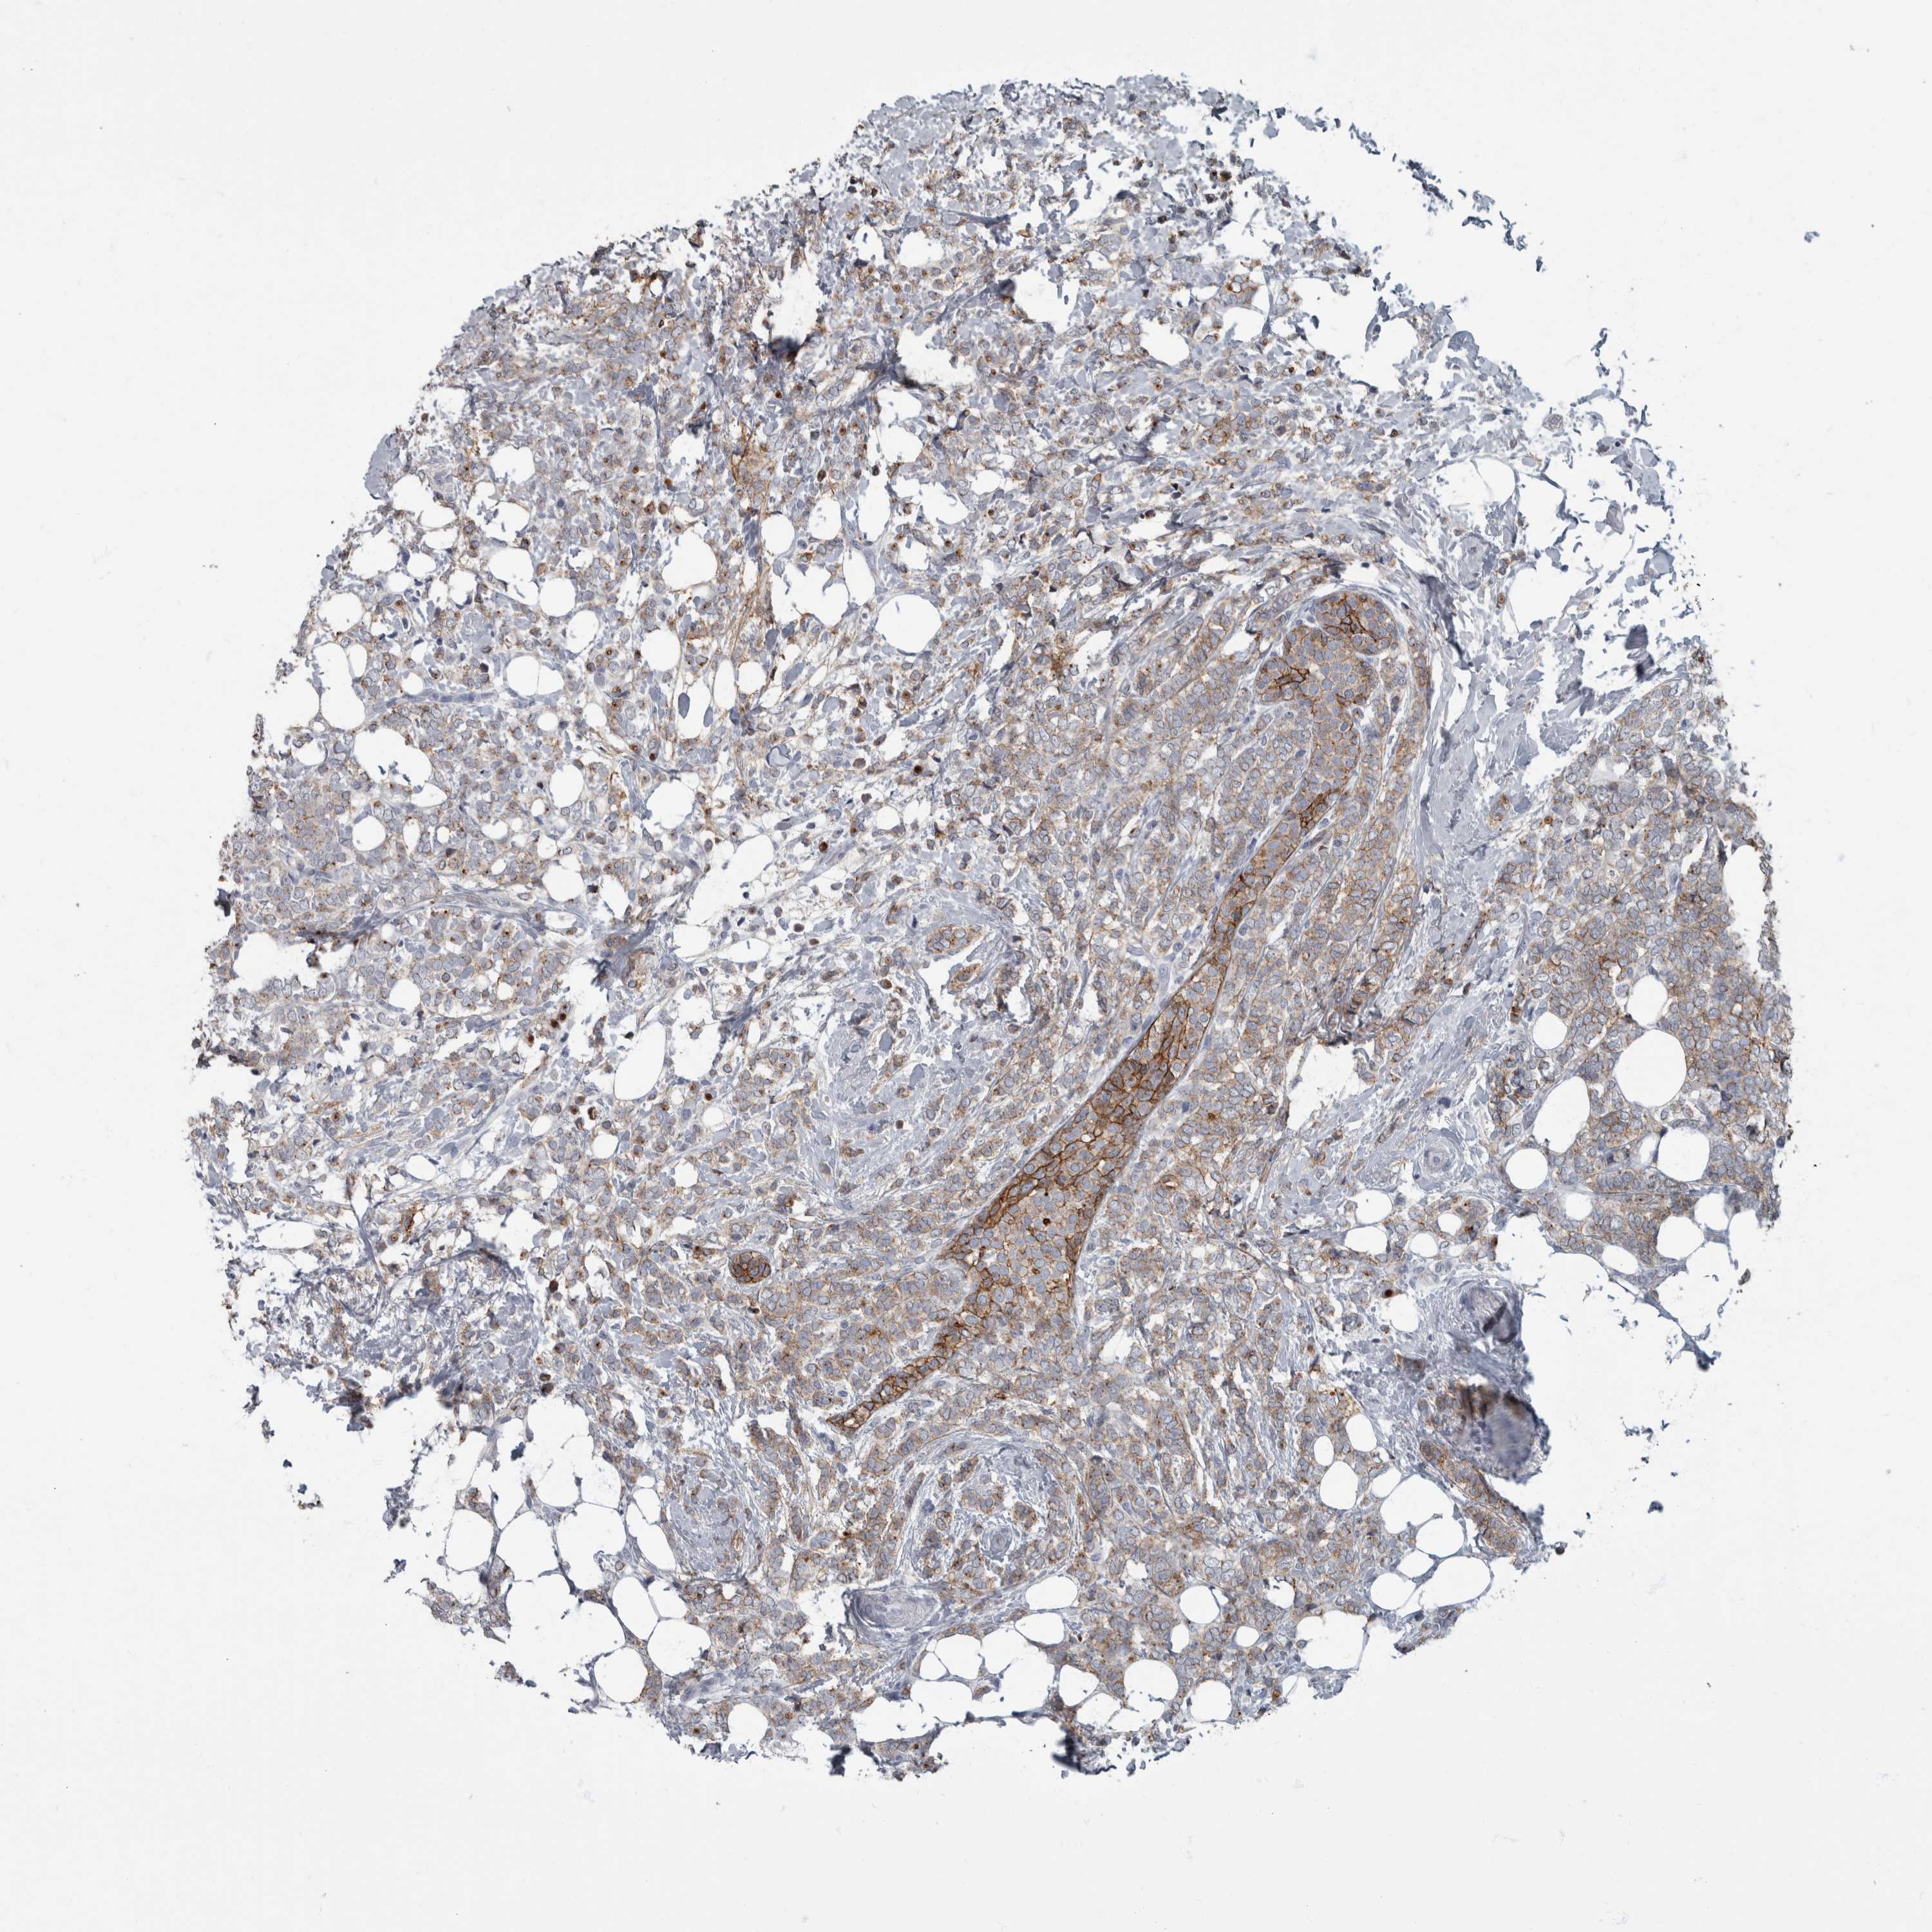

CANCER BREAST CANCER Show tissue menu

BRCA TCGA BRCA VALIDATION PROTEIN EXPRESSION